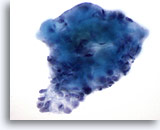

Figure 7

Breast FNA, Fibroadenoma.

This is another example of the branching appearance of ductal cells in fibroadenoma. 20x

Figure 7

Breast FNA, Fibroadenoma.

This is another example of the branching appearance of ductal cells in fibroadenoma.

20x